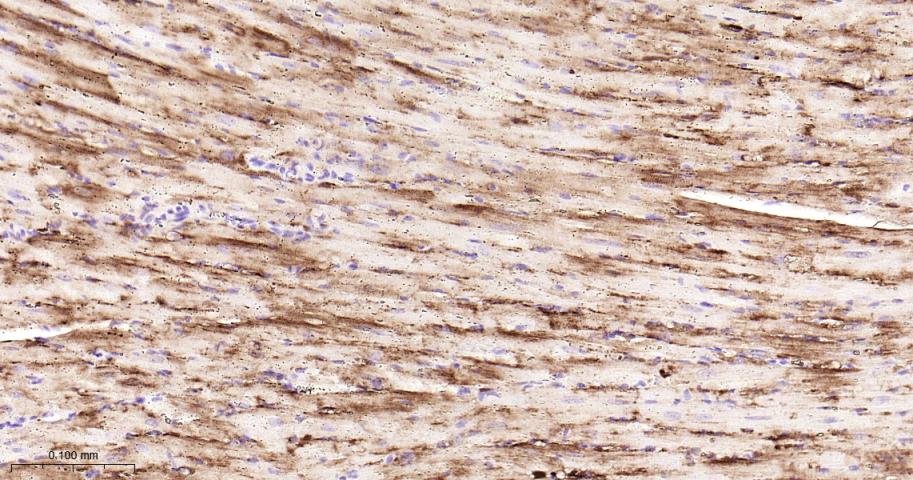

Paraformaldehyde-fixed, paraffin embedded Mouse Heart; Antigen retrieval by boiling in sodium citrate buffer (pH6.0) for 15 min; Antibody incubation with Hsp27 Monoclonal Antibody, Unconjugated(bsm-52757R) at 1:200 overnight at 4°C, followed by conjugation to the bs-0295G-HRP and DAB (C-0010) staining.

Paraformaldehyde-fixed, paraffin embedded Rat Heart; Antigen retrieval by boiling in sodium citrate buffer (pH6.0) for 15 min; Antibody incubation with Hsp27 Monoclonal Antibody, Unconjugated(bsm-52757R) at 1:200 overnight at 4°C, followed by conjugation to the bs-0295G-HRP and DAB (C-0010) staining.

Paraformaldehyde-fixed, paraffin embedded Human Heart; Antigen retrieval by boiling in sodium citrate buffer (pH6.0) for 15 min; Antibody incubation with Hsp27 Monoclonal Antibody, Unconjugated(bsm-52757R) at 1:200 overnight at 4°C, followed by conjugation to the bs-0295G-HRP and DAB (C-0010) staining.